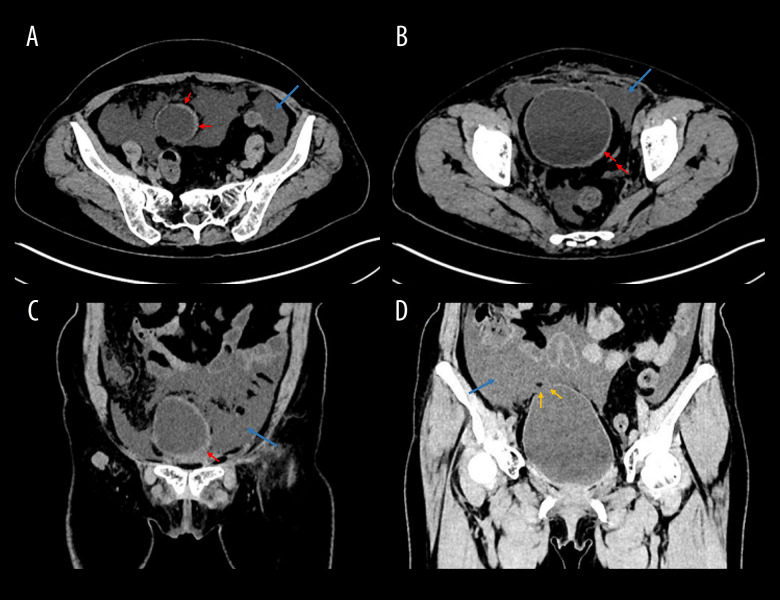

BACKGROUND Non-traumatic bladder rupture, a rare yet potentially life-threatening condition, can stem from diverse factors such as malignancies, bladder inflammation, or bladder diverticulum rupture. Pelvic radiotherapy, in extremely rare instances, can lead to radiation cystitis and subsequent bladder fistula formation. Patients with such conditions often present with abdominal pain, hematuria, oliguria, and urinary ascites. The diagnosis of radiotherapy-related bladder fistula poses significant challenges, particularly in patients with protracted illnesses and atypical abdominal symptoms, as it can be easily overlooked. CASE REPORT We present the case of a 60-year-old woman who, 14 years following a hysterectomy, bilateral adnexectomy, and radiotherapy for cervical carcinoma, developed recurrent abdominal pain and ascites. Initially, her symptoms were misattributed to gastrointestinal disorders. However, ascites analysis, which revealed markedly elevated creatinine and urea nitrogen levels in the ascitic fluid compared to serum, led to the suspicion of urinary ascites. The definitive diagnosis of an intermittent bladder fistula was confirmed through the instillation of a saline-methylene blue solution via the urinary catheter, which resulted in the drainage of blue ascitic fluid. CONCLUSIONS The diagnosis of vesical fistula is often challenging due to its diverse presentations and the possibility of being overlooked by CT. However, early recognition and appropriate management are crucial to prevent severe complications. This case highlights the importance of considering bladder fistula in the differential diagnosis of unexplained ascites and peritonitis, especially in patients with a history of pelvic radiotherapy or cystoscopic treatment.